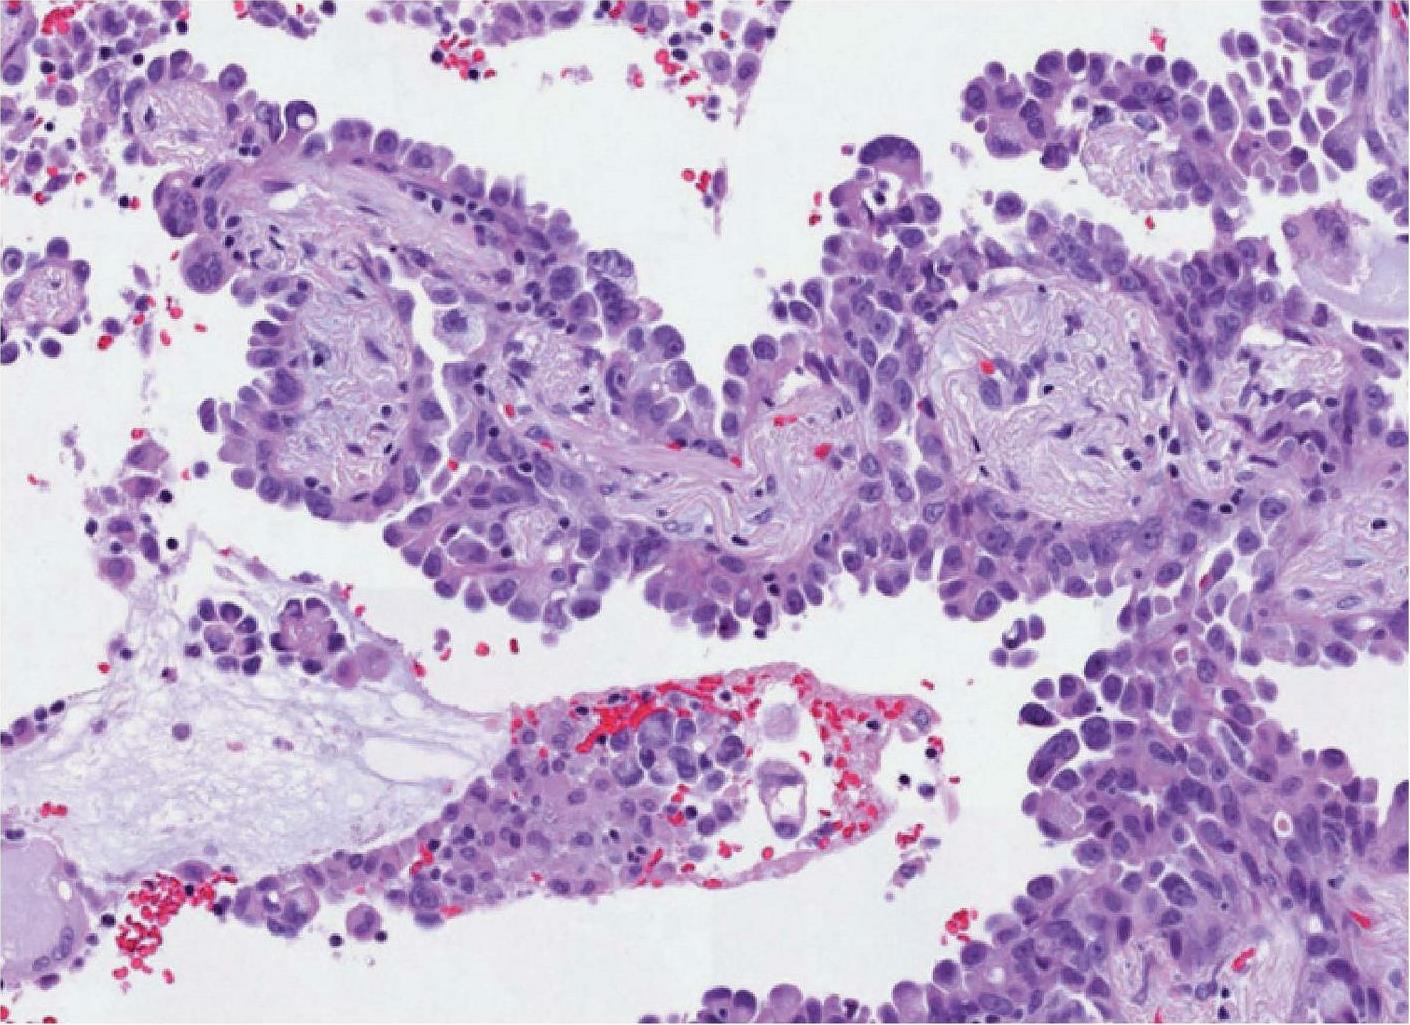

SP263克隆号检测平台及结果判读与22C3和28-8标准大致相同,判读结果以TC计算,不同的是若SP263仅有肿瘤细胞基底膜染色不能算作阳性,需基底膜及侧膜同时染色时才可判为阳性,根据肿瘤细胞PD-L1的表达分别为1%≤TC评分<5%、5%≤TC评分<10%、10%≤TC评分<50%、TC评分≥50%。图2-10和图2-11所示为肺浸润性腺癌HE染色图和PD-L1 (SP263)免疫组织化学染色图,图2-11显示肿瘤细胞基底膜及侧面均染色,应纳入PD-L1评估,TC评分≥50%。图2-12和图2-13所示为肺浸润性腺癌HE染色图和PD-L1 (SP263)免疫组织化学染色图,部分肿瘤基底膜及侧面均染色的肿瘤细胞(如黑色箭头所示),应纳入PD-L1百分比评估中,而染色的免疫细胞应排除PD-L1评估;部分肿瘤细胞仅基底膜染色,侧面未染色(如红色箭头所示),不应纳入阳性肿瘤细胞。不同TC评分的NSCLC PD-L1 (SP263)免疫组织化学染色结果如图2-14至图2-17所示。

图2-10 肺浸润性腺癌HE染色图(×400) [7]